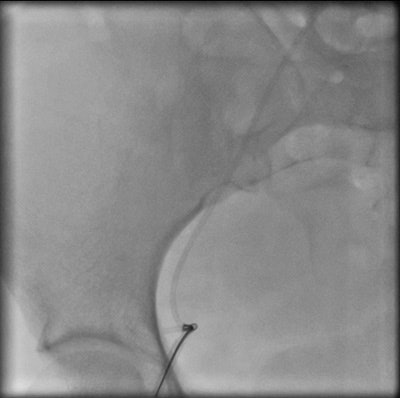

Percutaneous retrieval of the retained fragment of the fractured portacath catheter was successfully accomplished on the second attempt. Following prepping of the right groin, the right femoral vein was punctured and an 8 French sheath was inserted. Selective catheterization of the right ventricle was performed using a 6 French catheter. A 25-mm snare was used to capture the migrated retained fragment. It was then removed successfully without immediate complications.